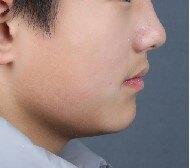

治疗前

11岁小男孩,主诉龅牙,牙齿不整齐。

检查:侧貌突,开唇露齿。上颌前突,下颌后缩,上前牙前突10mm左右,咬合深,咬至上颌粘膜,上下牙弓狭窄,牙列拥挤不齐。